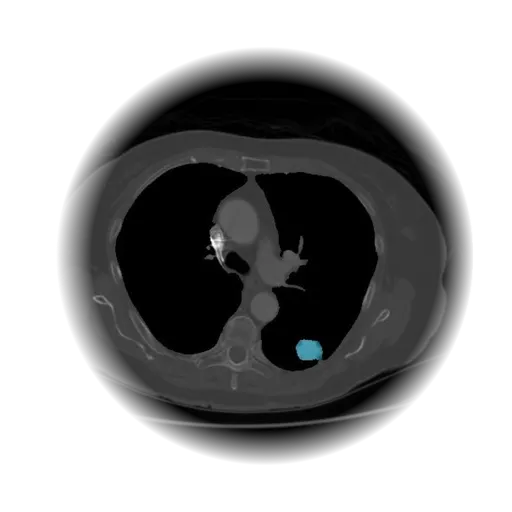

Lung Nodule Detection and Tracing Across Scans

Obvios.ai utilizes cutting-edge artificial intelligence to meticulously detect and track lung nodules, facilitating swift and precise diagnostics, thereby ensuring superior care and timely intervention for patients.